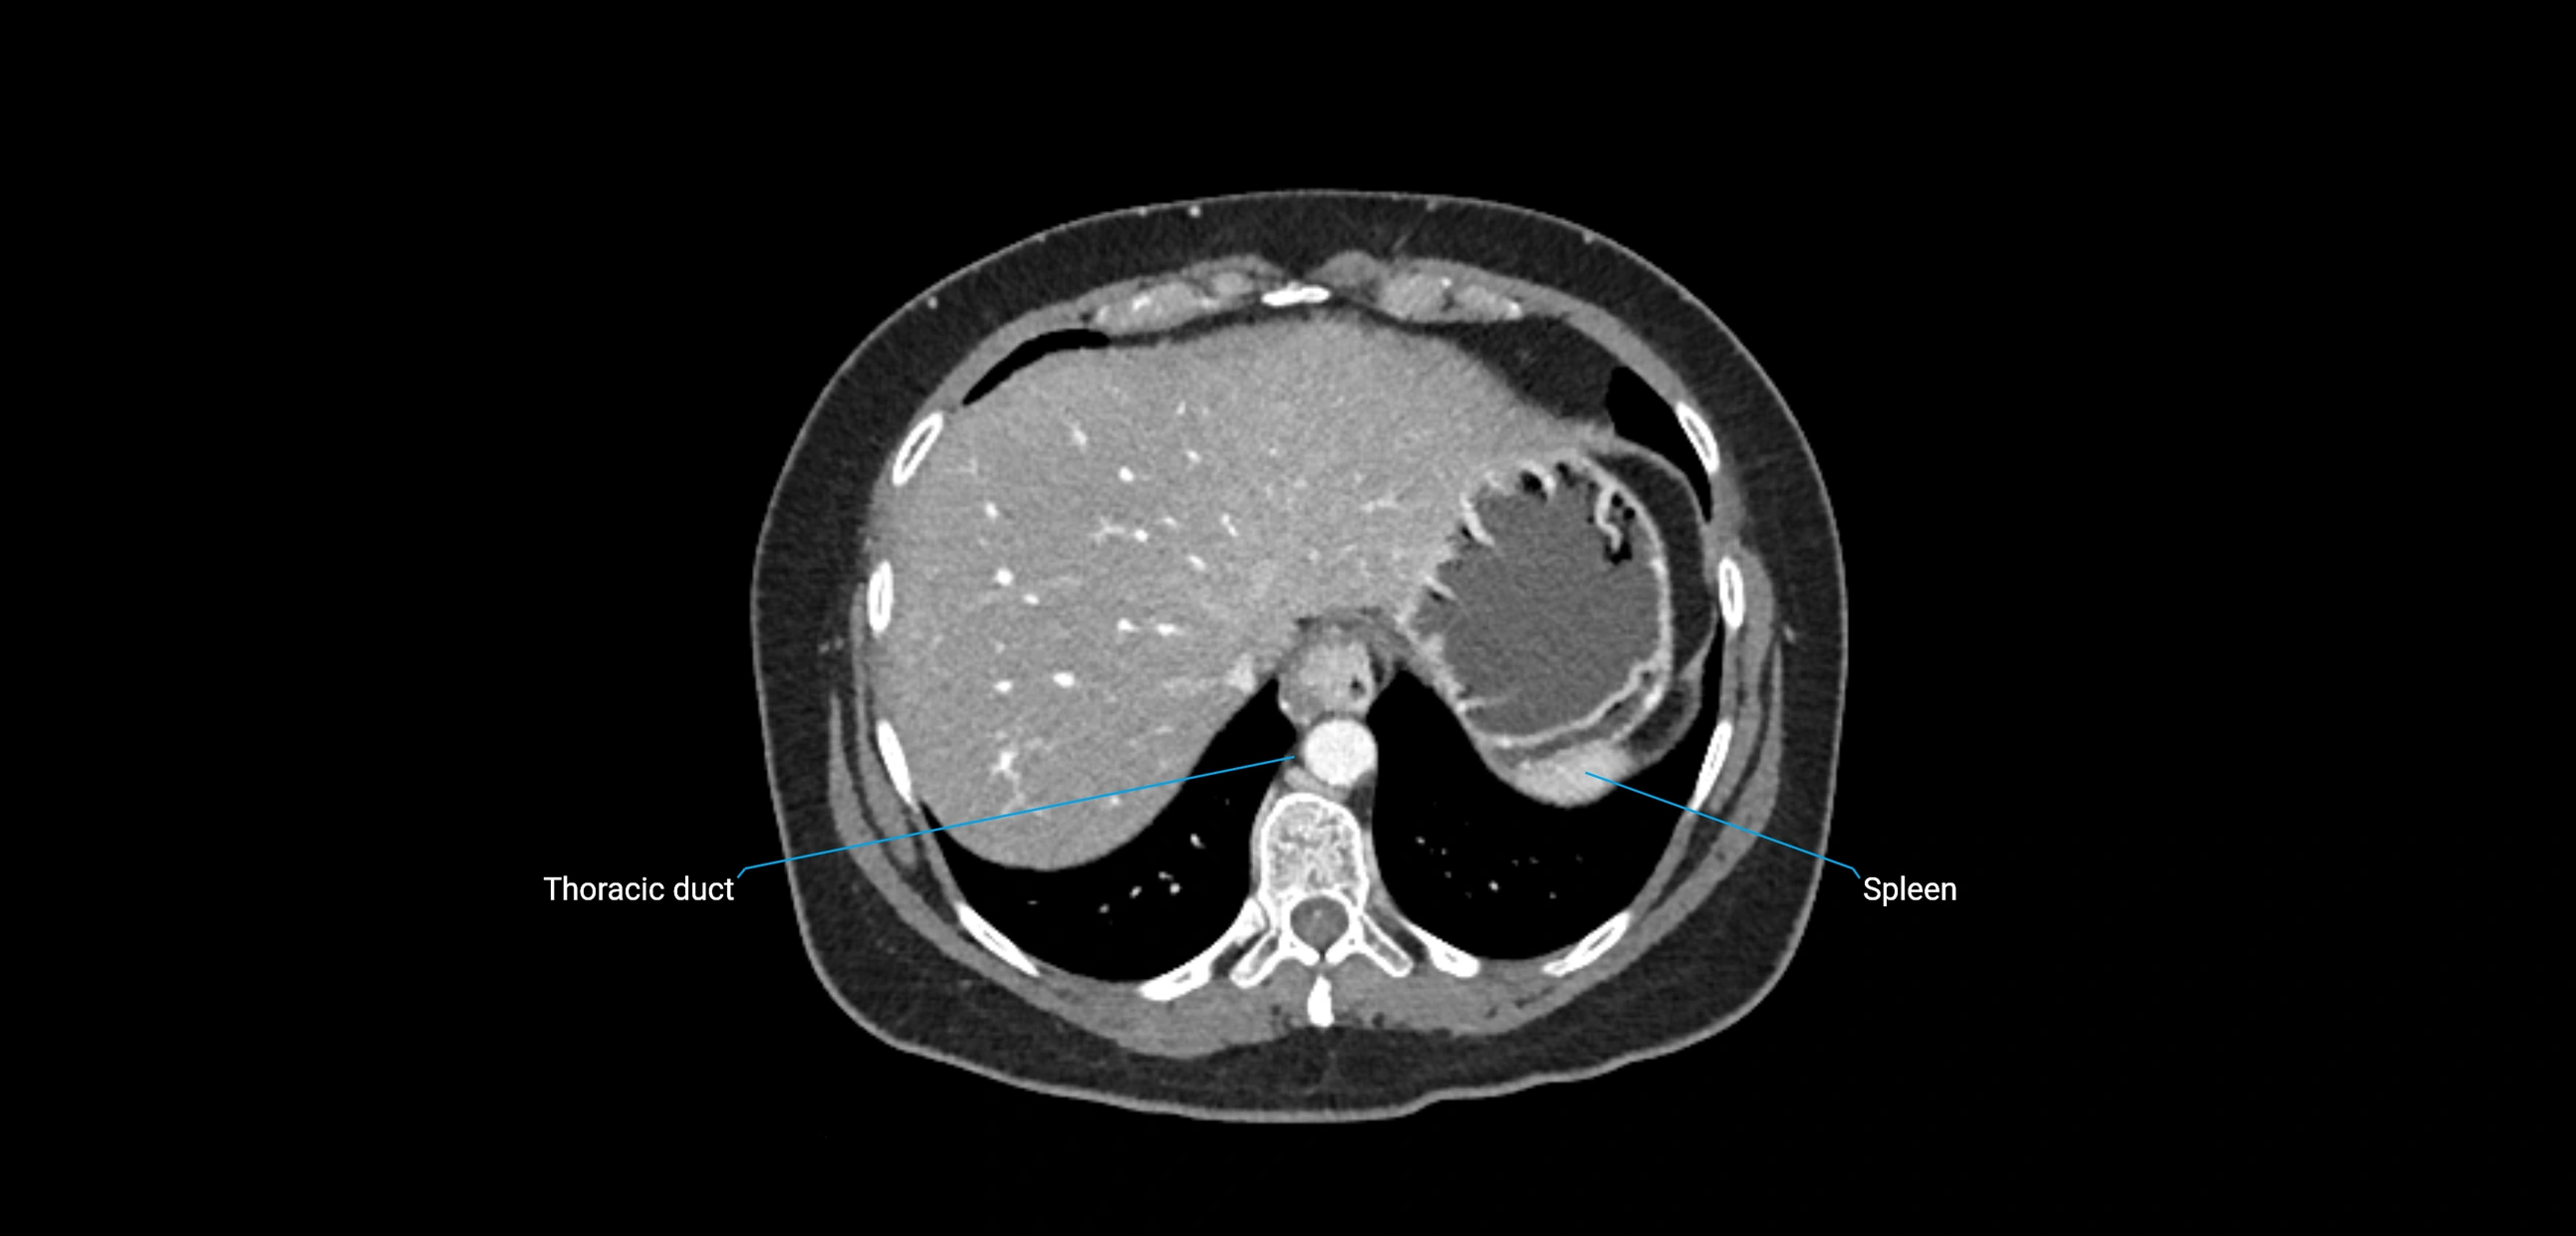

CT image

image